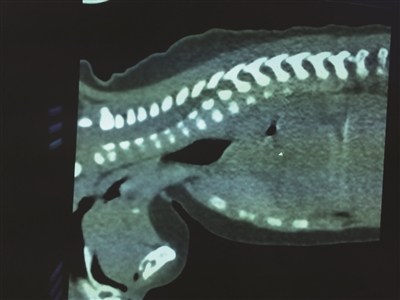

黄豆卡在孩子食道中,已经吸水涨大近一倍。

樊明月告诉扬子晚报记者,6天前就是这粒黄豆将男婴食道梗阻。所有的食物因为那粒黄豆,堵塞在了食道内,无法进入胃里。从CT上看,这个梗阻的部位宽大约两三厘米,长约10厘米。由于黄豆在食管中已经待了至少6天,黄豆已经吸水涨大近一倍,和他的一节小手指头粗细差不多大了,“看上去,好像是快发芽了。”后续治疗大约两三天之后,男婴迅速恢复,目前已出院。